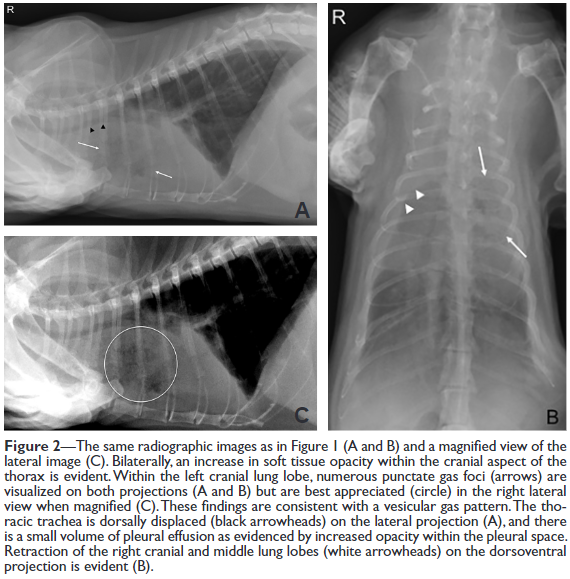

이번 논문은 고양이 폐염전 환자들에 대한 증례이니 참고하고 고양이도 폐염전이 충분히 생기니 상황에 따라 감별진단 리스트에 포함시키는 것으로.

이외에 JAVMA에 투고된 케이스 리포팅 자료도 참고하길